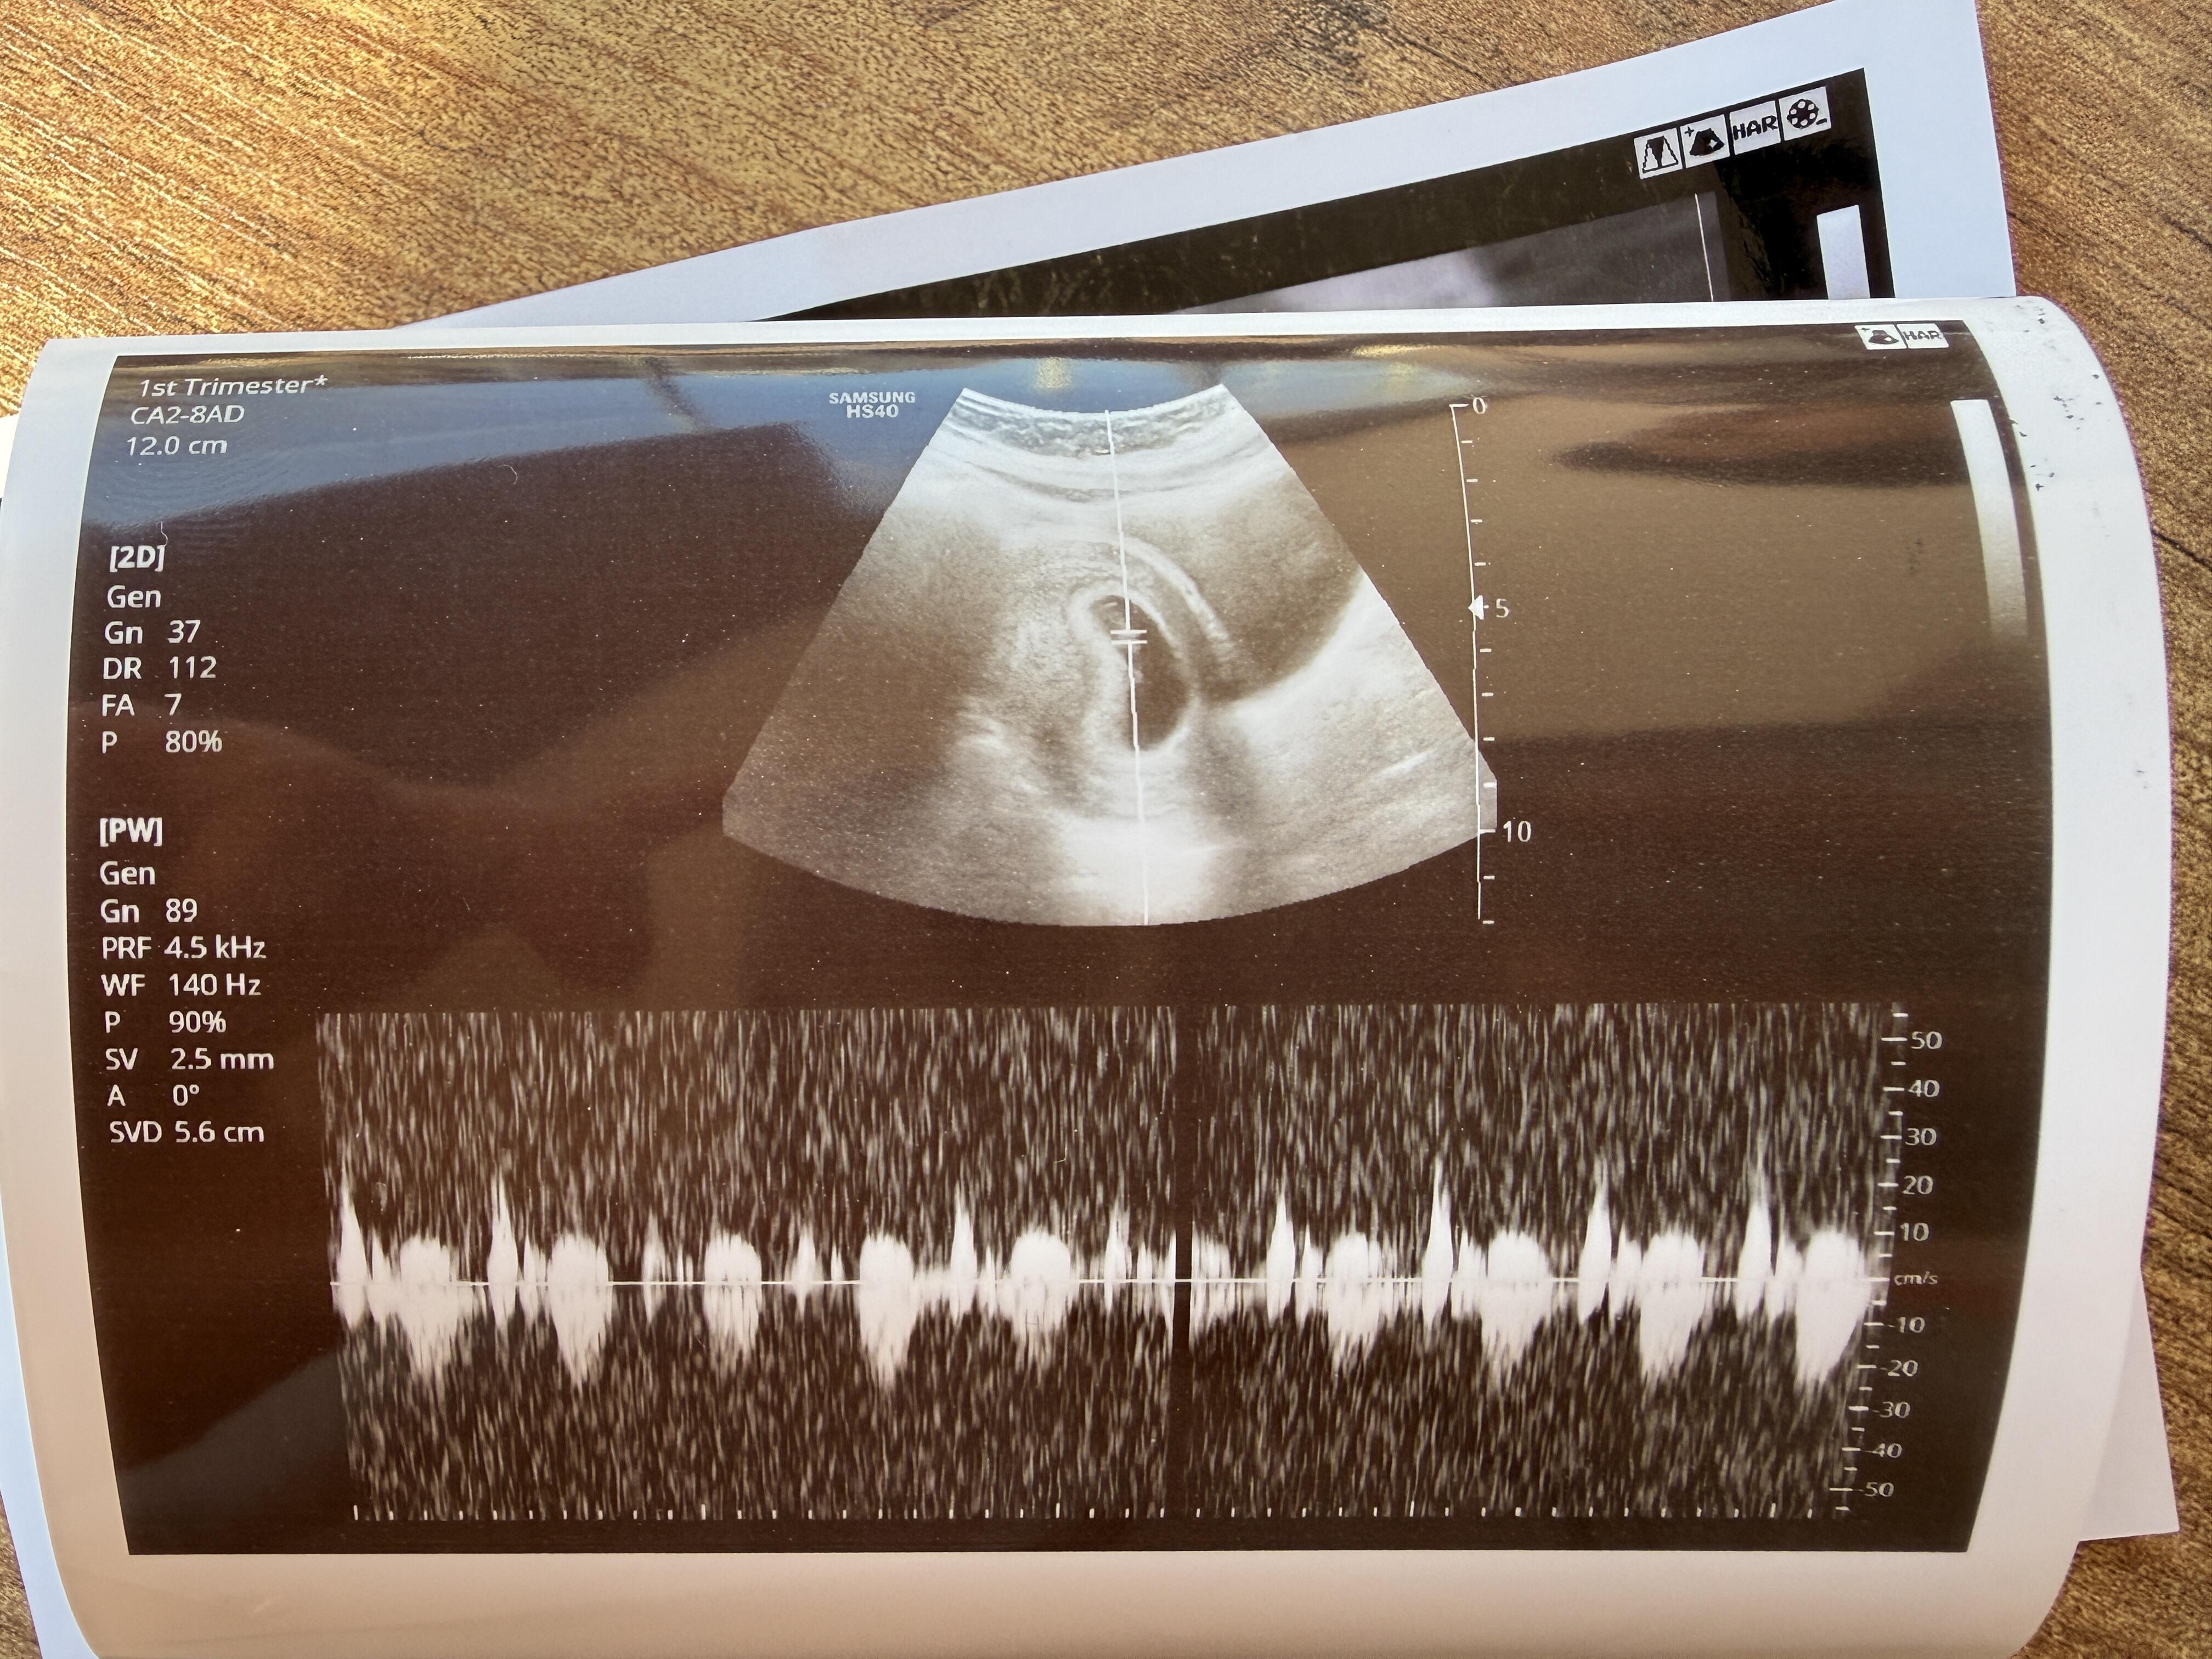

Bu yüzde 80 erkek bence

Bacak arasından bir şey var Kordon ise ama kız bebek gibi duruyor canim

Erkek bebek canım ama biraz daha gelişine tekrar at